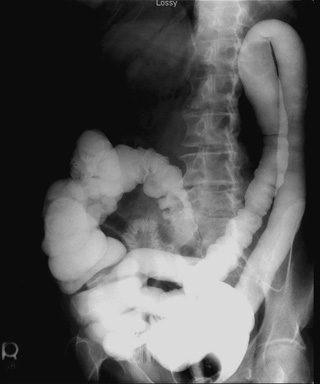

- Post-evacuation radiograph - patient prone, PA

view, vertical central ray, 14" x 17" cassette